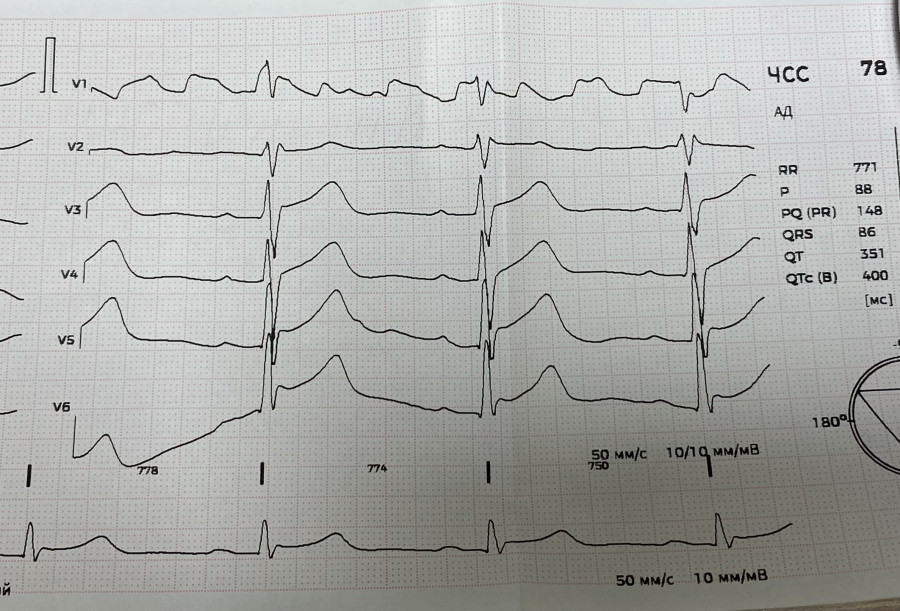

М 37. Перикардит эксудативный на фоне ушиба сердца. ЭКГ до дренажа.